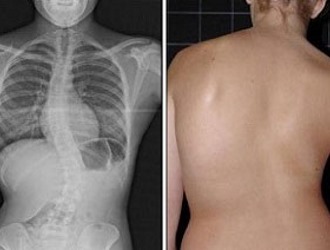

Сколиоз представляет собой распространенное заболевание, затрагивающее опорно-двигательный аппарат. Это состояние характеризуется искривлением позвоночника в форме дуги и поворотом позвонков вокруг своей оси.

Наиболее часто сколиоз выявляется у детей – около 80% всех зарегистрированных случаев приходится на детский возраст. Это связано с активным ростом костей и влиянием неблагоприятных факторов, таких как неправильная осанка, недостаточная физическая активность, неравномерное распределение нагрузки (например, ношение сумки или рюкзака на одном плече), а также сон на слишком мягкой поверхности и другие.